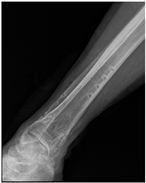

Patient C was a 42-year-old female with a left tibial fracture and underwent ORIF in February 2019. There were no known comorbidities for her. Four months after ORIF, she developed increasing tenderness, a local skin rash, a nonhealing wound, and intermittent clear discharge on the left leg. Physical examination revealed bullae formation, scaling with an erythematous base within a well-defined margin. Range of motion, distal motor function, circulation, and sensory function were intact. Radiographs confirmed a union of the tibia at the fracture site. There was no purulent drainage or fever, and the white blood cell count was 11,900/μL, which was not sufficient to confirm infection in the absence of purulence or systemic signs. She underwent a patch test for hypersensitivity, and the result showed an allergy to metal complexes. Under the impression of suspected hypersensitivity to the implants, she underwent the removal of the implants. The allergic symptoms were resolved after the implant removal. Follow-up at two months and one year showed improvement in symptoms (Figure 2).